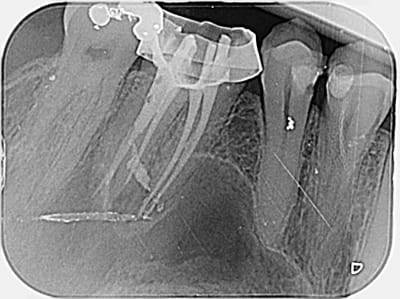

J'ai refais une retroalveolaire et je trouve que ce n'est pas très nette au niveau de l'apex de la racine MV.

si c'etait le leger depassement sur la racine MV il aurait eu mal au bout de 3 jours .Il faudrait plutot penser a 1 MV2(deuxieme canal dans la racine MV)

J'ai cherché mais je n'en ai pas trouvé. Peut-être une bifurcation apicale ?